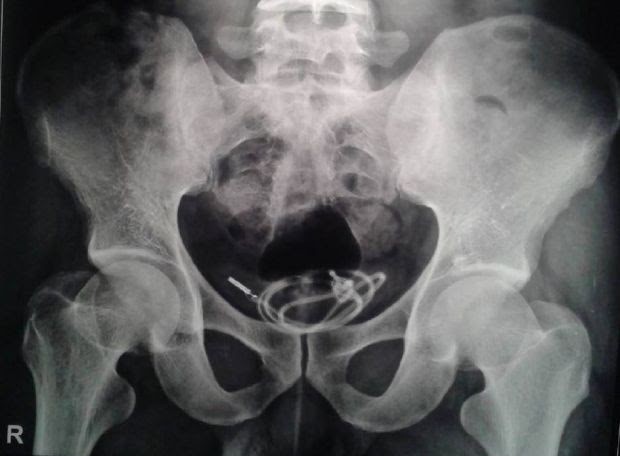

Всички знаем, че лекарската тайна се спазва много стриктно, но понякога информацията може да спести много бъдещи болки. Снимката на този 35-годишен мъж показва ясно, че през последните няколко часа не е успял да отиде до тоалетната и да свърши една от най-щастливите работи на мъжкото съсловие.

Рентгентът разкрил истинската причина проблема - аудио кабел, който минал през уретрата и блокирал потока на течност, която да отделяме след 3 бири.

Опитът да се извади по същия начин бил напълно невъзможен, защото на края присъствал и прекрасен възел. Наложила се операция, която да освободи канала.